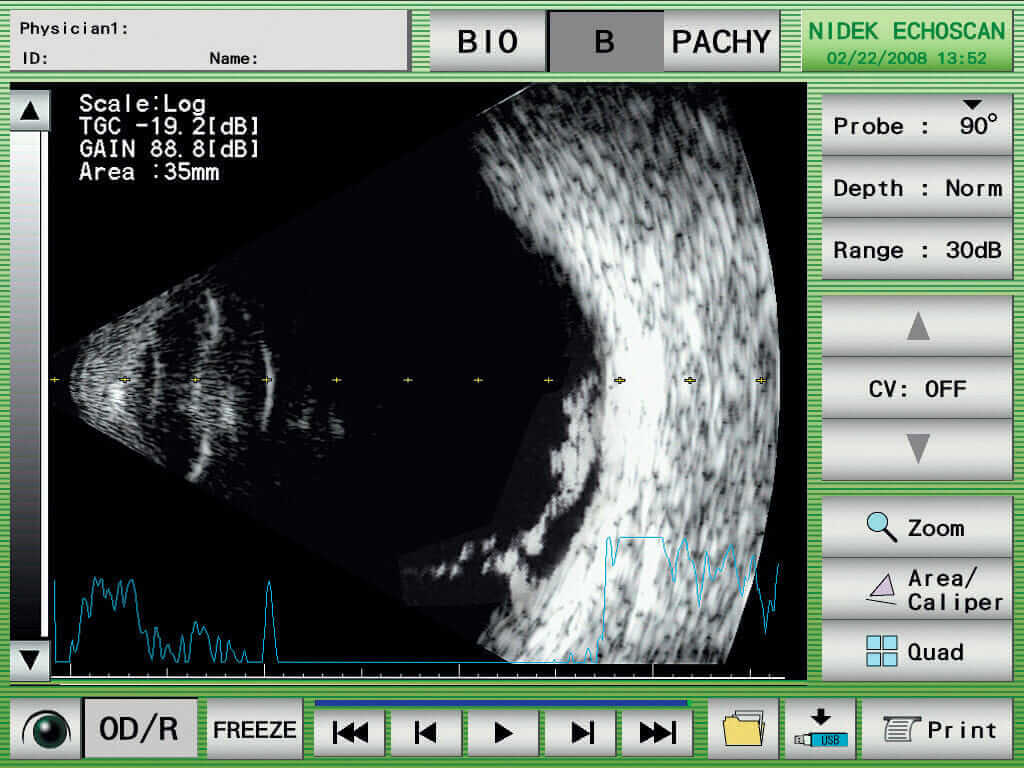

Nidek US-4000

Ultraschall A/B Scan mit Pachymtrie

Kompaktes, modular ausbaubares Instrument. Durch das kontrastreiche Display können B-Scan sehr gut auf dem Display live angesehen werden. Verschiedene Bearbeitungsprogramme lassen eine perfekte Lokalisation zu. Sehr einfache Bedienung durch den Touch Scren Bildschirm, schnelles abspeichern von Messungen, Druckmöglichkeit durch den integrierten Printer oder USB Interface für Datenexport. Zur Kalkulation von IOL und Patientenverwaltung. IOL Formula (SRK, SRK2, SRK-T, Binkhorst, Holladay